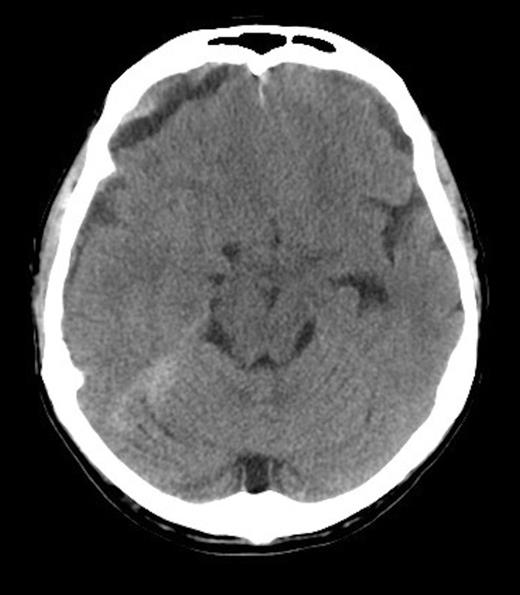

He received further platelet and plasma transfusion to correct his INR of 3.5, and was taken to theatre where a right parietal craniotomy and left parietal burrhole were performed to evacuate the SDH. Intraoperatively, the dura was noted to be thickened and subdural membrane tissue was obtained for histopathology. This was consistent with metastatic adenocarcinoma of the prostate (Figure 3 & 4). The patient recovered well day one post-operatively with no neurological deficits. His level of consciousness rapidly deteriorated on day two post-operatively, with no evidence of haematoma recurrence or neurosurgical complication on repeat CT Brain. The patient subsequently died on post-operative day four.

Histopathology Right subdural membranes: Immunoperoxidase staining for PSA (x4)